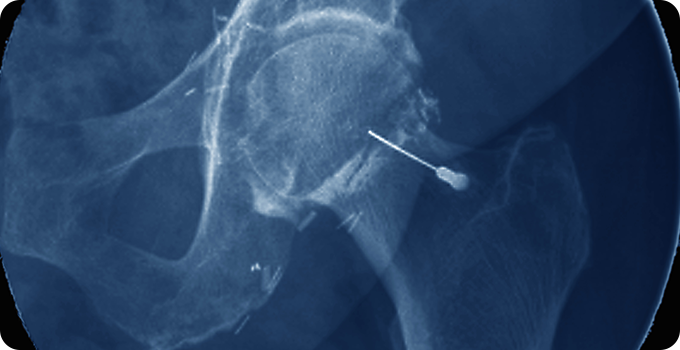

재생주사치료 치료 사진

초기 - 재생주사치료

퇴행성 고관절염의 재생주사치료는 PRP 주사, DNA 주사, 콜라겐 주사를 사용해 연골 재생과 염증 완화를 돕습니다. PRP는 성장인자로 회복을 촉진하고, DNA 주사는 윤활과 복구를 지원하며, 콜라겐 주사는 연골 보호와 재생에 기여합니다. 환자의 상태에 따라 선택되며 부작용이 적고 회복 기간이 짧은 장점이 있습니다.